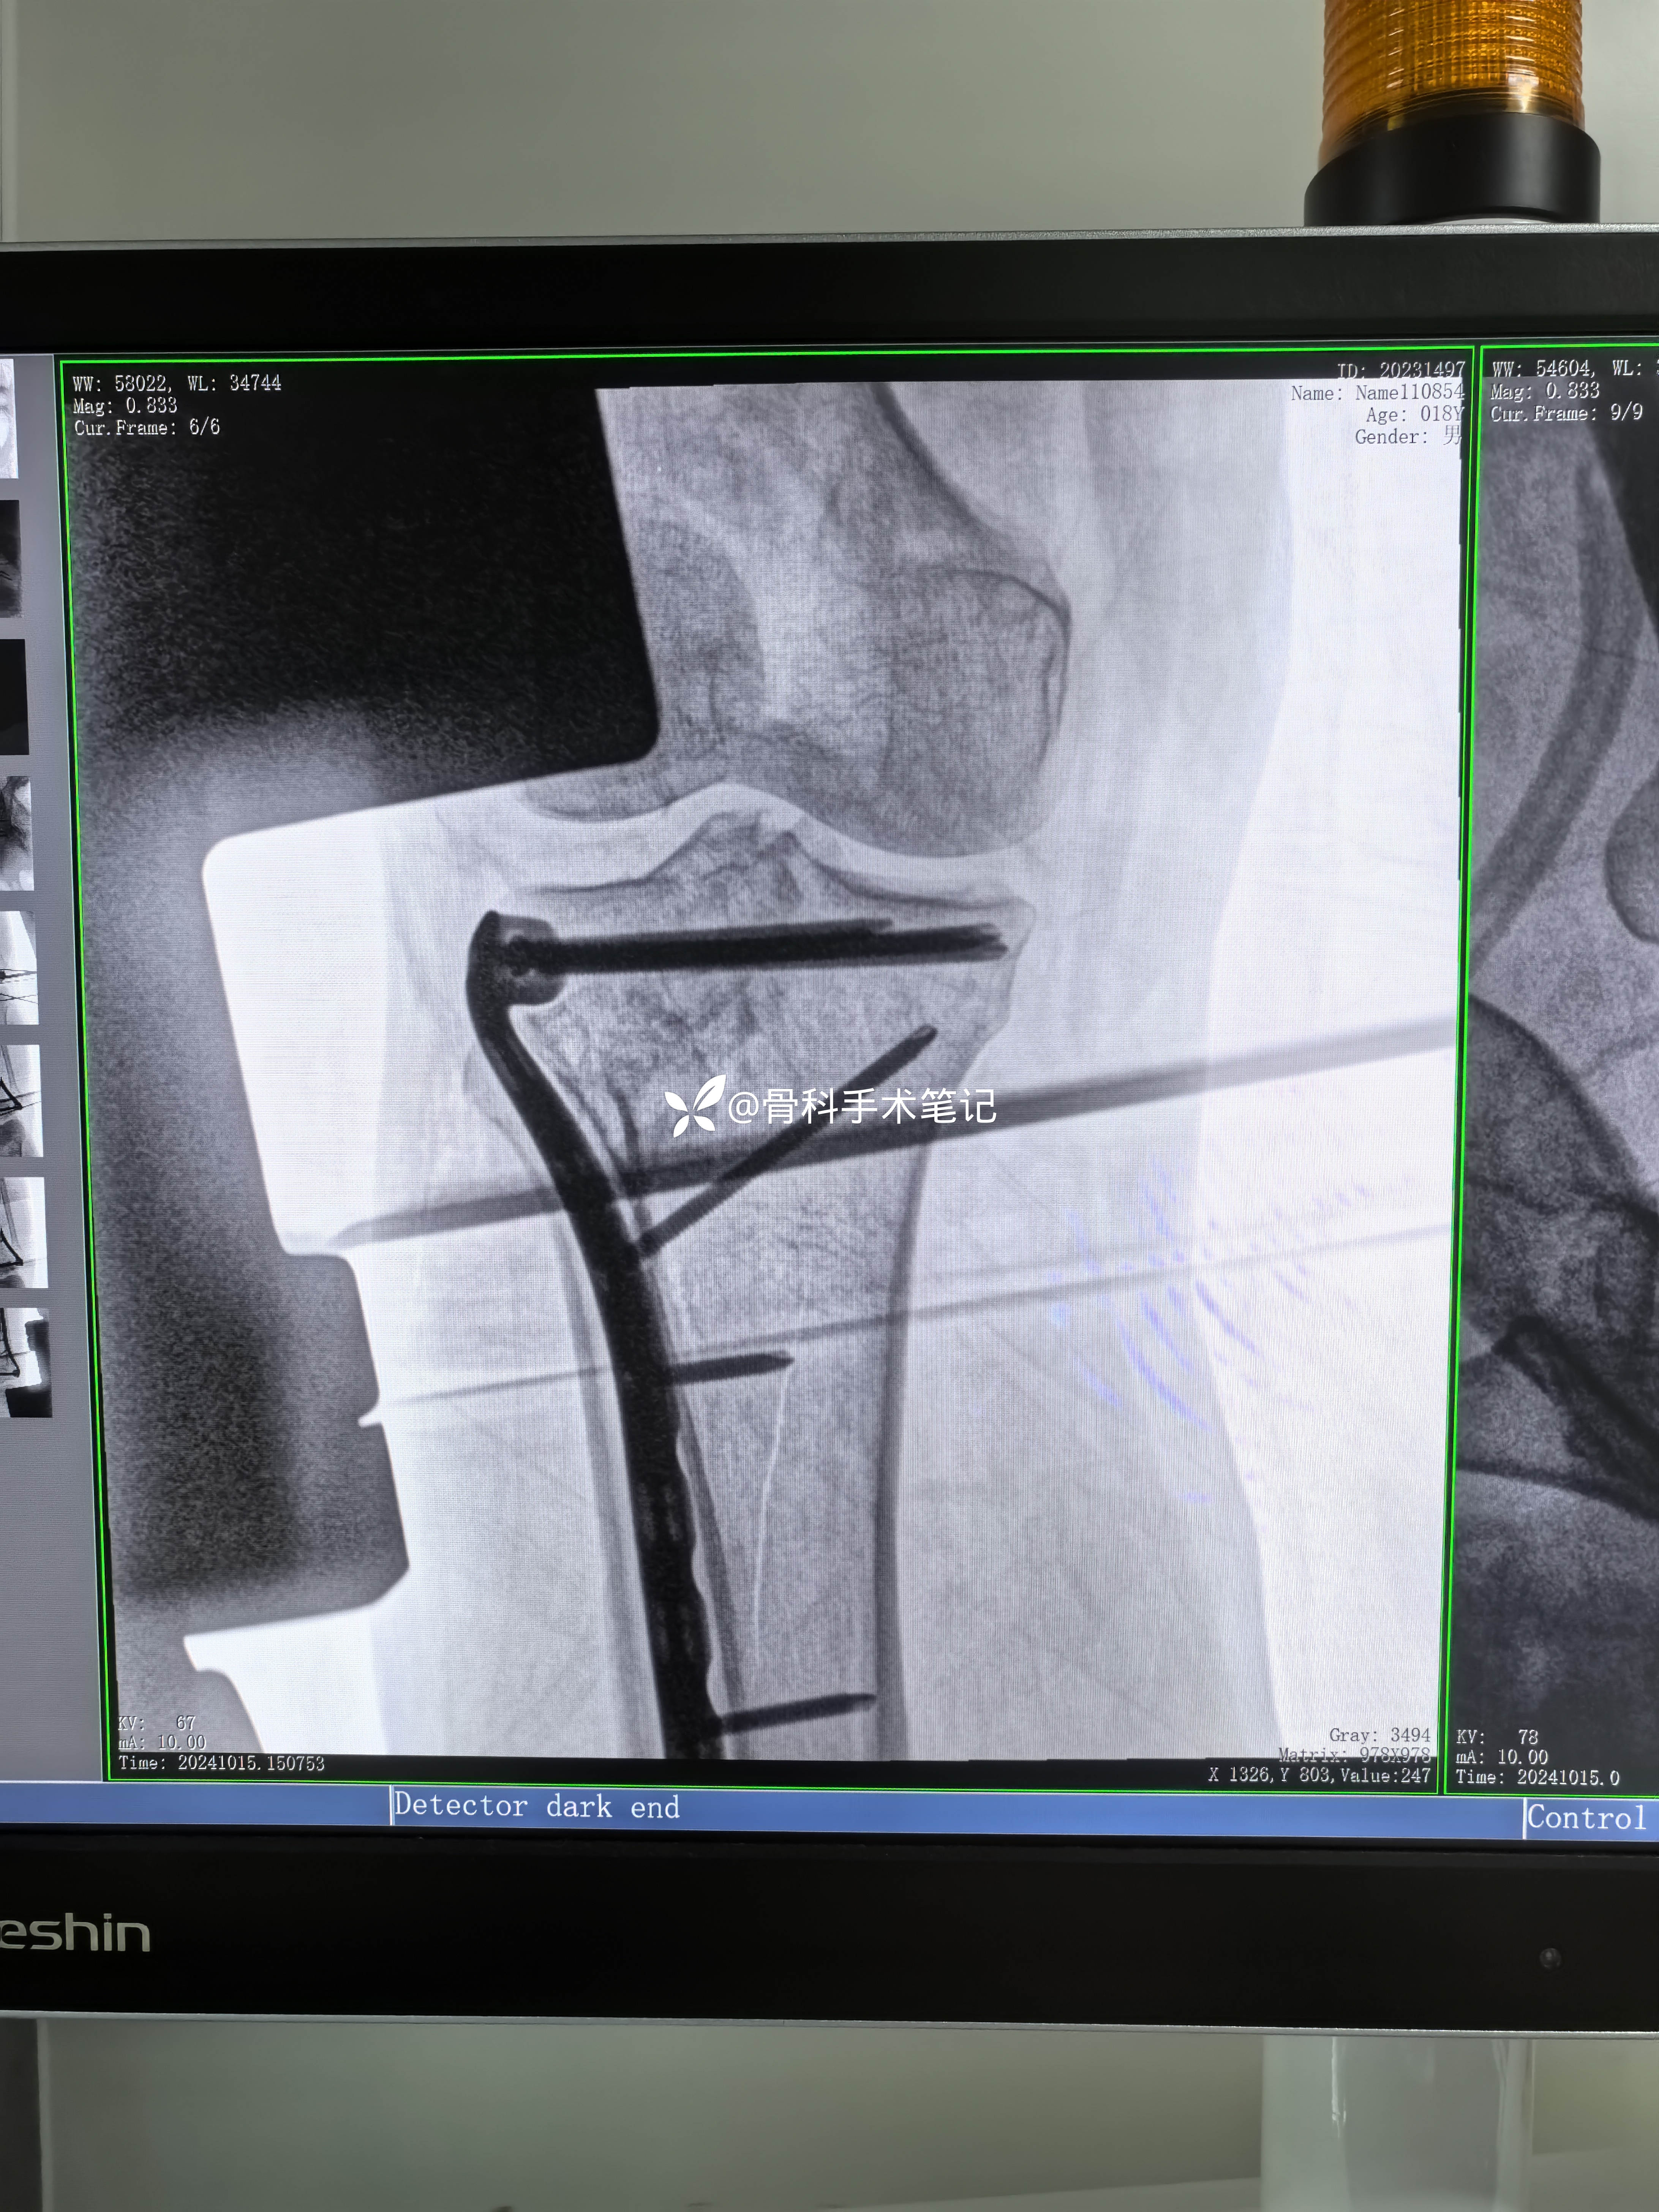

术后影像资料